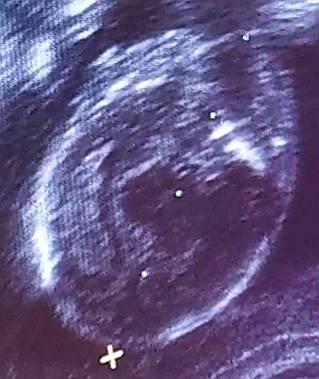

Schaut mal, ist es hier nicht noch deutlicher? :-) Seht ihr die beiden zarten Striche?

Bild zu

Wenn das das Geschlecht sein soll dann tippe ich auf ein Mädchen LG

Dann sage ich auch Mädchen.

Mädchen sagte auch die FÄ Wäre cool, weil mein Sohn sich sehr eine SCHWESTER wünscht

Mädchen